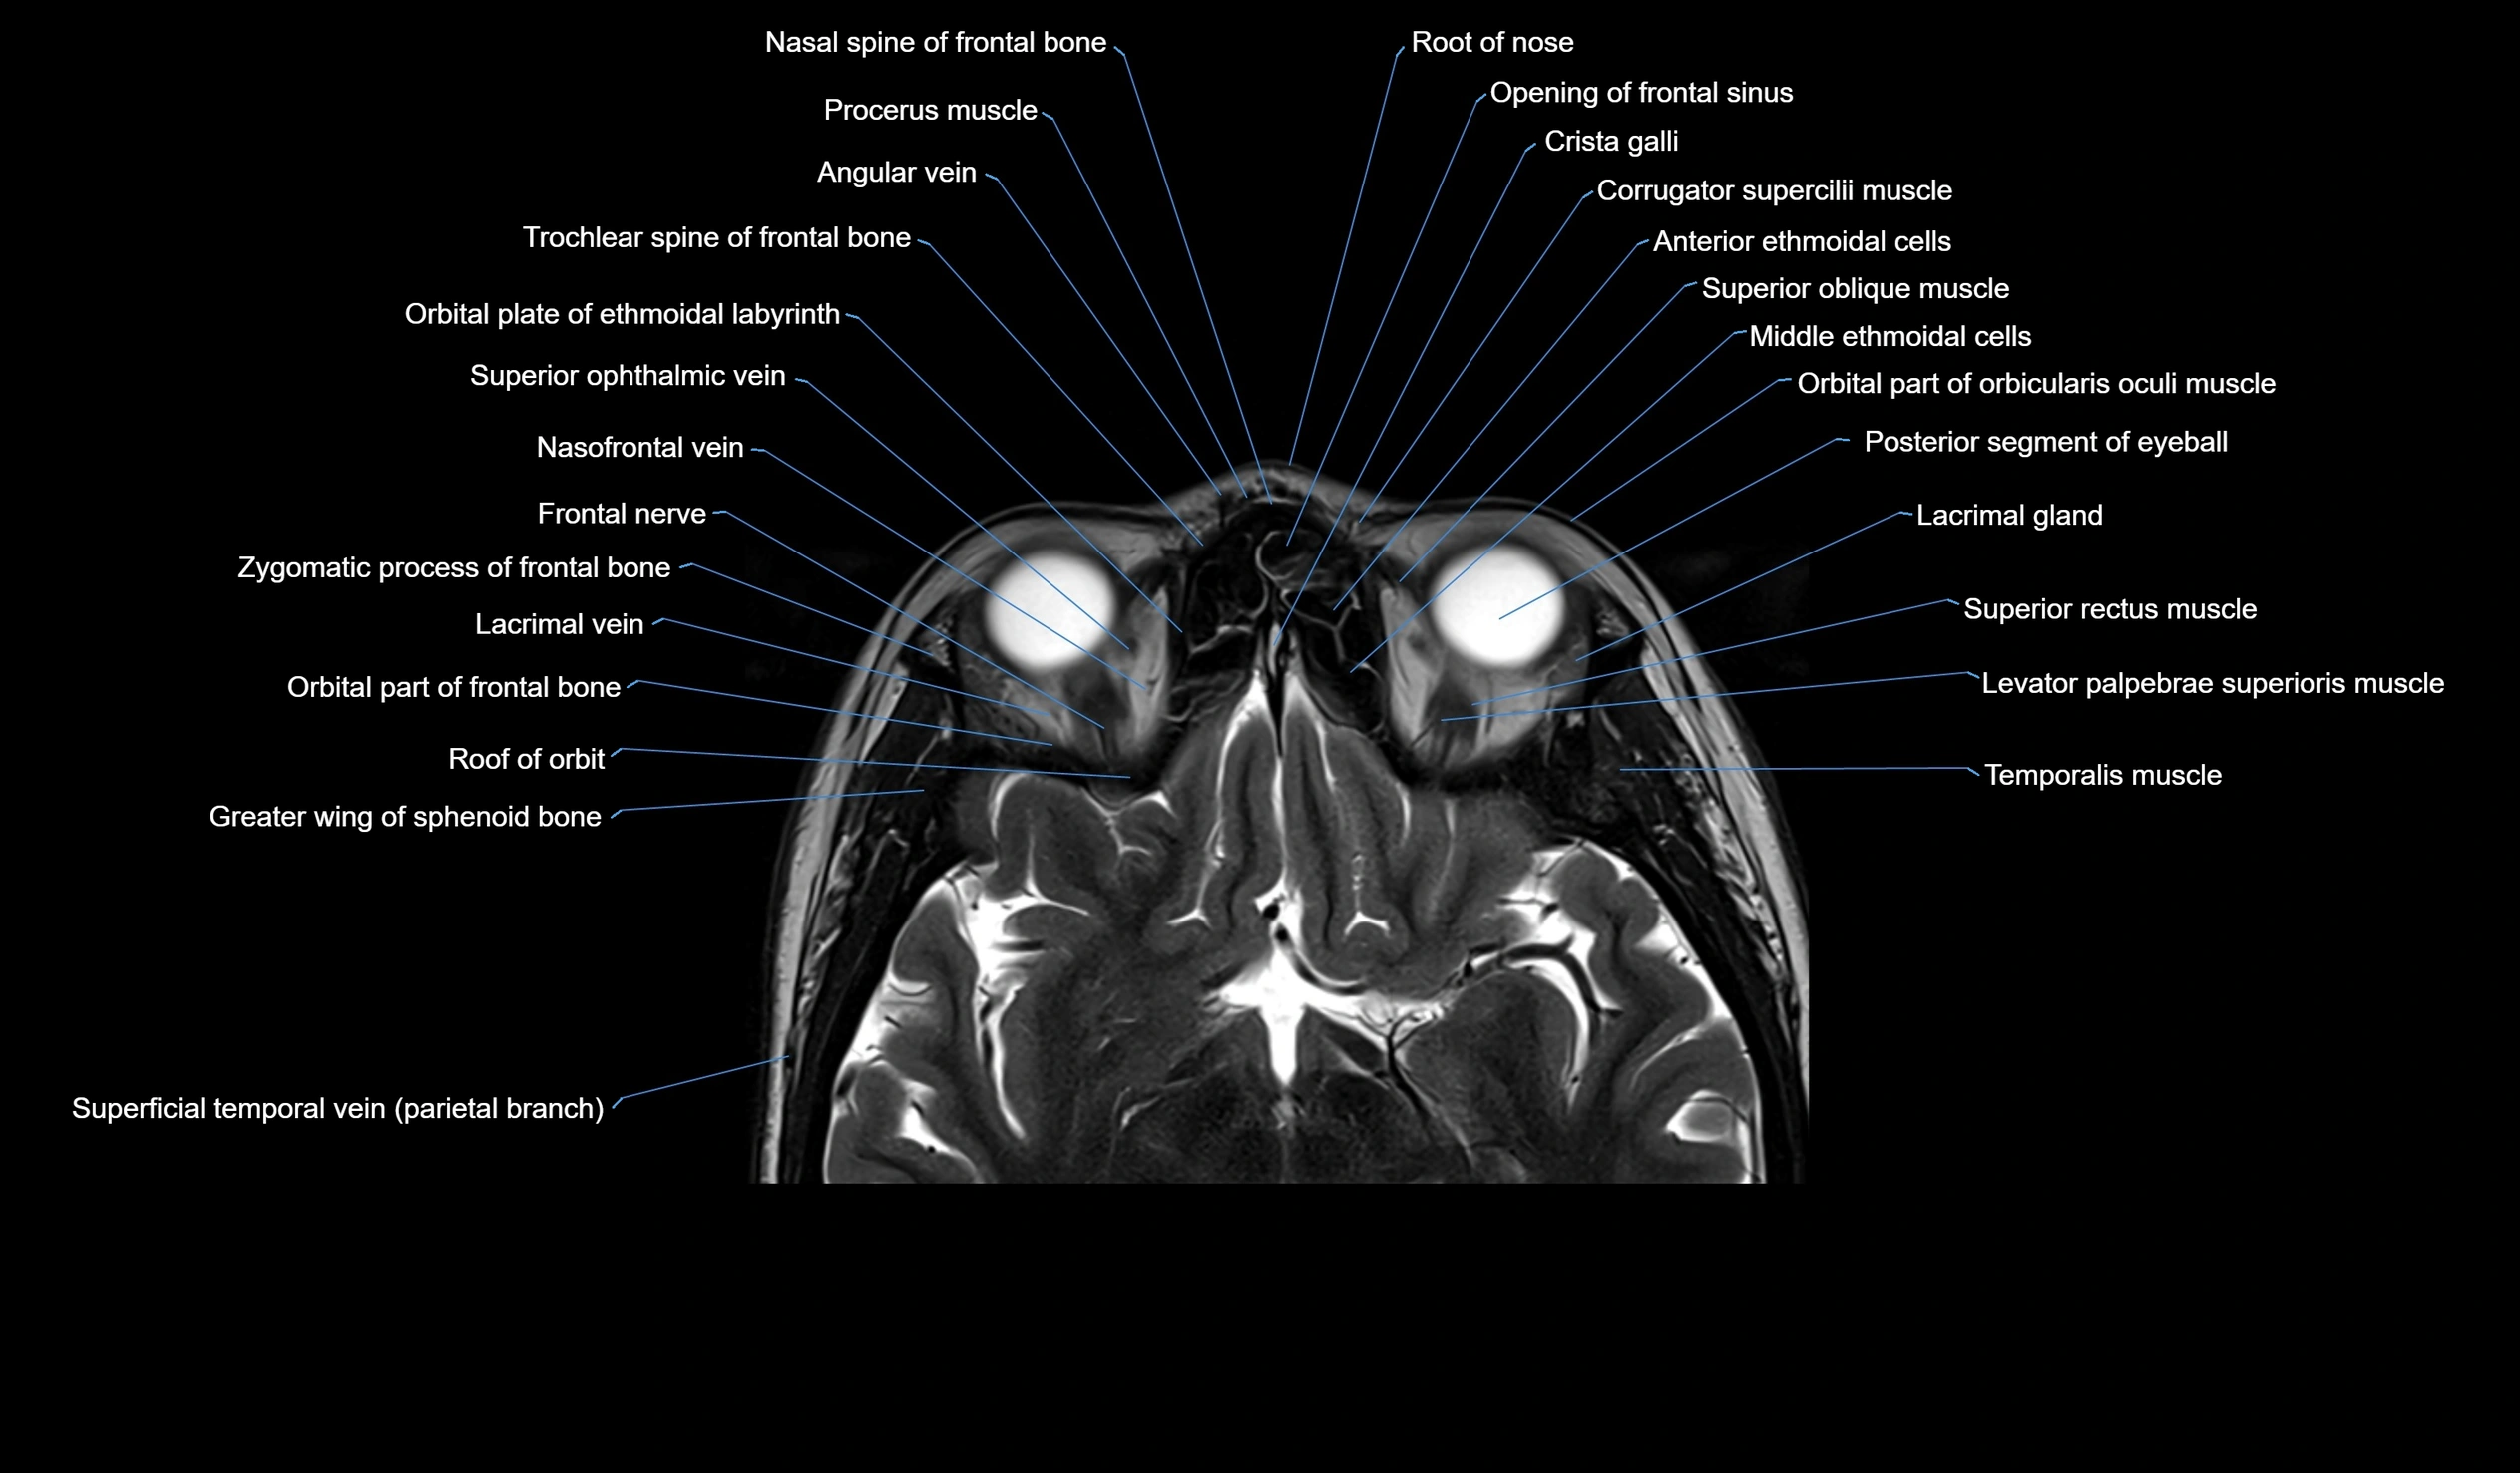

MRI images